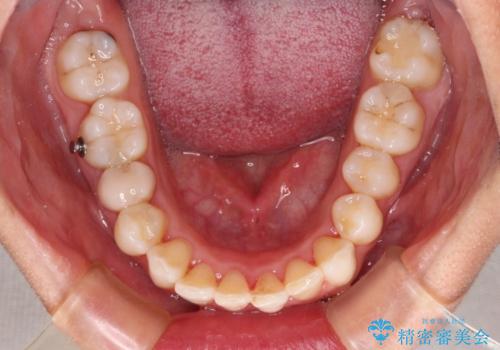

下顎善の叢生をもう少し改善したかったのですが、患者様は十分に整ったとのことで治療を終えることになりました。